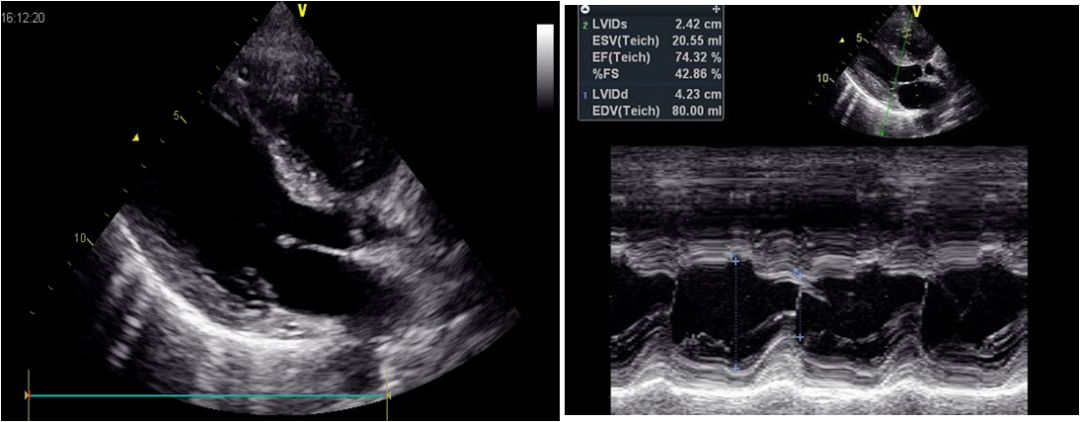

出院时心脏彩超

左心室舒张末内径42mm,EF:74%